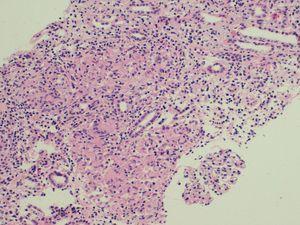

The patient was a 56-year-old woman with no allergies or substance abuse and with no medical history of interest or regular medical treatment. She was referred to emergency services by her family doctor after an abnormal blood test (creatinine 8mg/dl), carried out to study a toxic syndrome of 6 to 7 months evolution with a weight loss of 10 kg. She had an analysis carried out 5 months earlier in a check-up at work which highlighted a Hb level of 11 g/dl and creatinine level of 1.7 mg/dl. The patient had normal blood pressure in the physical examination, and pale mucous membranes; everything else was normal. Analyses showed results of Hct/Hb 28 %/9.6 g/dl, urea/creatinine 192/9.4 mg/dl (estimated GFR 4ml/min), calcium 10 mg/dl, FENa 10. Proteinuria 0.6 g/24 h, and sediment was normal. PTHi and vitamin D levels were normal. Patient was negative for HbsAg, HCV and HIV. Immunological study: ANA, anti-DNA, ANCA, serum complement and immunoelectrophoresis were normal or negative. The Rose Bengal test for anti-Brucella antibodies was negative. Urine culture in Löwenstein-Jensen medium was negative. The PPD skin test was negative. ACE levels were 189 U/l (8-52 U/l). The chest x-ray, abdominal ultrasound and CT scan of chest, abdomen and pelvis were normal. No significant changes were found in the eye and ENT examinations. A jugular catheter was inserted and haemodialysis was begun. A percutaneous kidney biopsy was performed showing 10 glomeruli, 2 of them sclerotic, the rest with normal appearance. Large amount of granulomas comprised of epithelioid cells and Langhans multinucleated giant cells without necrosis (Figure 1) were observed in the interstitium. The histochemical techniques to detect fungi and acid-alcohol resistant bacilli were negative. Treatment began with prednisone at 1 mg/kg/day. The patient had conserved diuresis and haemodialysis was well tolerated. After four weeks of corticosteroid treatment, a progressive improvement in kidney function was observed, enabling her to stop the replacement treatment. At present, 4 months after starting treatment and with a dose of 0.3 mg/kg/day, she has a plasma creatinine level of 2.8 mg/dl (GF 19 ml/min) and a normal level of ACE.

Figure 1. Kidney cortical